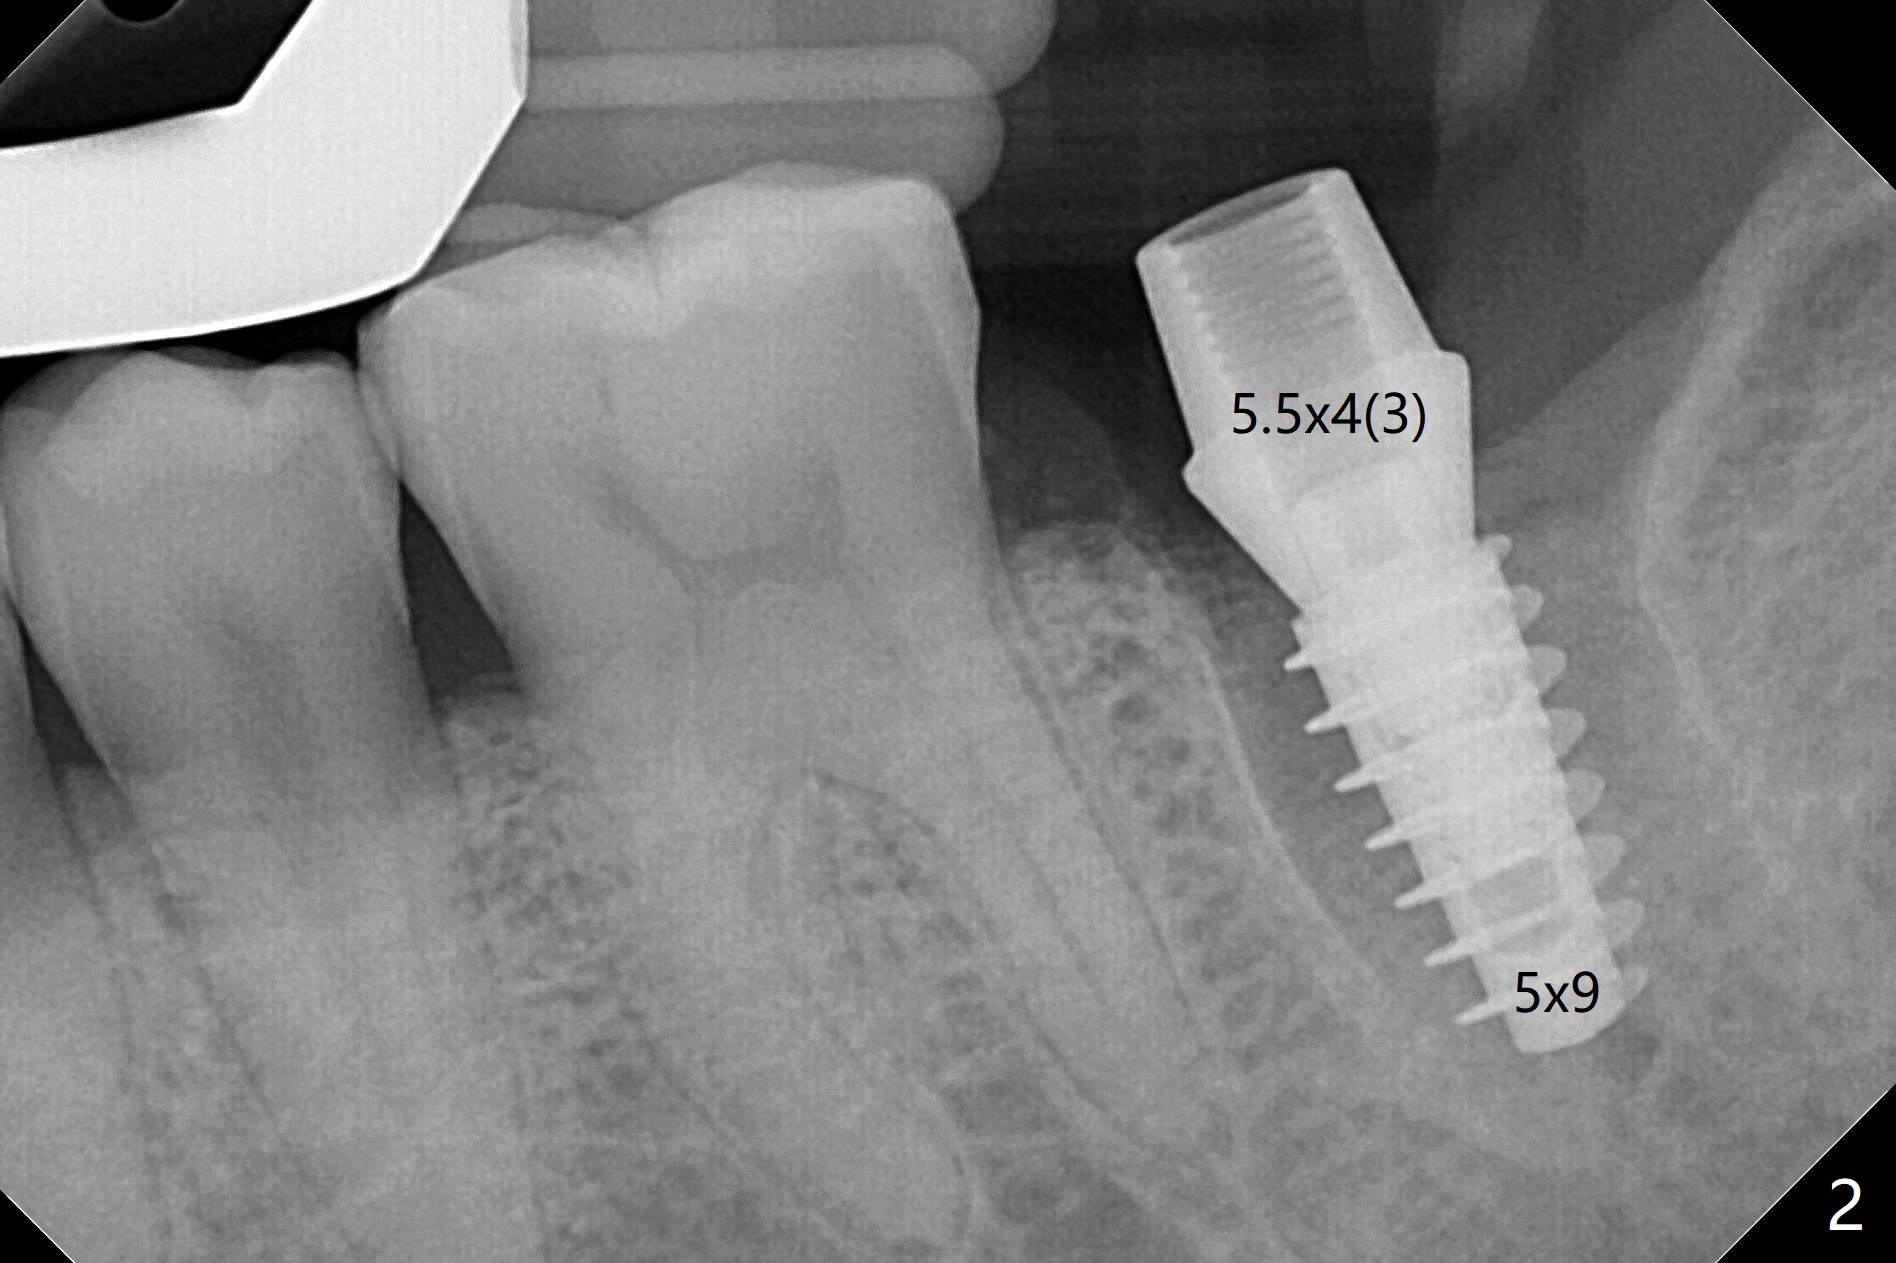

18号牙远中龈下龋齿,在导板指引下,使用4.0x8.5毫米钻头后,钻洞建立在中隔(图一:S)近中舌侧,5.0x9毫米植体似乎还没有超出牙槽窝轮廓(图二),已经取得35Ncm扭力。放置基台后,放入足够粘性骨粉(图三:*),然后制作临时牙冠,结合PRF,固定骨粉。由于植体没有接触牙槽嵴,那里骨质吸收将是轻微的,而骨质再生显著。